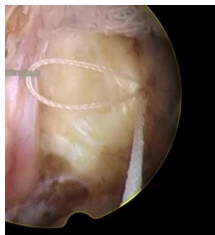

一次性纖維環(huán)縫合器的臨床應(yīng)用:

隨著纖維環(huán)縫合器縫合纖維環(huán)技術(shù)的推廣,很多學(xué)者做了相關(guān)的臨床研究。Parker等對(duì)30例纖維環(huán)縫合患者進(jìn)行了2年隨訪研究,零復(fù)發(fā)且椎間隙高度無(wú)改變。Bailey等通過(guò)對(duì)750名患者對(duì)比研究,發(fā)現(xiàn)纖維環(huán)非縫合組在術(shù)后2年時(shí)的再手術(shù)率較縫合組高45%。研究發(fā)現(xiàn),縫合纖維環(huán)可提高椎間盤生物力學(xué)性能,縮短其愈合時(shí)間,同時(shí)也減緩椎間盤組織的退變進(jìn)程。修復(fù)后纖維環(huán)回縮可減少對(duì)神經(jīng)根刺激,可有效消除疼痛癥狀。目前LDH髓核摘除術(shù)后復(fù)發(fā)的主要病因?yàn)槔w維環(huán)缺損、持續(xù)重復(fù)應(yīng)力因素等,比較明確的病因?yàn)槭中g(shù)導(dǎo)致的纖維環(huán)缺損,總結(jié)得出髓核突出少、纖維環(huán)缺損嚴(yán)重者術(shù)后的復(fù)發(fā)率高。縫合后纖維細(xì)胞受到反復(fù)牽拉應(yīng)力刺激,可促進(jìn)纖維環(huán)的愈合和防止炎癥因子的產(chǎn)生。纖維環(huán)愈合產(chǎn)生的瘢痕組織可減輕關(guān)節(jié)突關(guān)節(jié)的應(yīng)力作用??p合纖維環(huán)可提高術(shù)后髓核“再水化”,促進(jìn)腰椎功能恢復(fù)。纖維環(huán)縫合益處:閉合裂口;降低術(shù)后復(fù)發(fā)率及再手術(shù)率;減輕髓核組織的免疫學(xué)反應(yīng)和炎癥介質(zhì)的外滲;有利于髓核的再生修復(fù)。要點(diǎn):切口大小以5mm的線形縱切口較佳,8mm以上需平行或交叉縫合2針;縫合針距離邊緣2~3mm為宜;縫合前,應(yīng)行邊緣探查,尋求無(wú)佳的縫合點(diǎn)。目前纖維環(huán)縫合面臨的重要問(wèn)題是如何改善或降低縫合處的應(yīng)力積累,受應(yīng)力積累影響瘢痕組織及神經(jīng)纖維可能侵入椎間盤,可引起盤源性疼痛。有學(xué)者對(duì)比研究得出,單針簡(jiǎn)單縫合,可降低術(shù)后復(fù)發(fā)率,雙針交叉或平行縫合療效更好,而改良荷包縫合,術(shù)后能避免髓核再次突出,生物力學(xué)完整性可得到更好保留。

一次性纖維環(huán)縫合器手術(shù)中注意事項(xiàng):

①適度增大開窗,便于縫合器的擺放及調(diào)整;

②切開纖維環(huán)時(shí)避免傷及內(nèi)側(cè)的神經(jīng)根及硬膜囊;

③摘除髓核時(shí),避免損傷切口兩側(cè)的纖維環(huán),盡量保留纖維環(huán)殘端的長(zhǎng)度和厚度以便于縫合;

④縫合時(shí),纖維環(huán)縫合器的扳機(jī)應(yīng)朝向術(shù)者對(duì)側(cè),避免因扳機(jī)遮擋影響術(shù)中穿刺;

⑤直針穿刺時(shí)旋鈕要旋轉(zhuǎn)到位,標(biāo)志線對(duì)齊,避免打成空結(jié);

6.?從纖維環(huán)切口的中1/3 處縱向縫合,避免縫線一側(cè)。